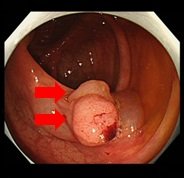

- 大腸内視鏡検査

| 大腸の病変の有無を調べる検査です。本検査では大腸ポリープの有無や経過観察、大腸粘膜の炎症等の診断などを目的としています。本検査でも、病変の状態によってはその場で治療を行うことがあります。 | ||||

|||

| 大腸ポリープ | 削除+止血クリップ | |||